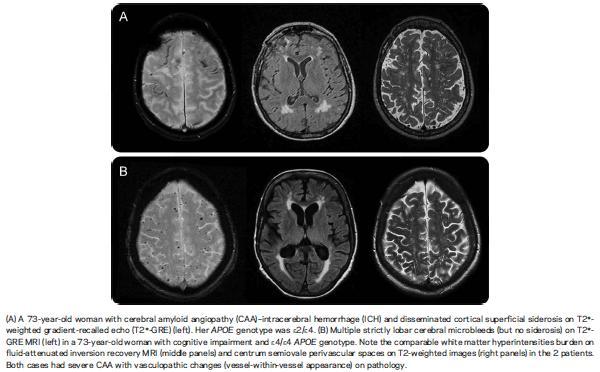

Potential markers include the apolipoprotein (APO) E ε2 genotype and imaging markers such as superficial siderosis and centrum semiovale white matter perivascular spaces. Superficial siderosis is not specific to CAA, being the result of any cause of chronic cerebral or spinal subarachnoid leakage of blood. Enlarged perivascular spaces could relate to small haemorrhages in the more distant past.

Imaging features of white matter changes, enlarged perivascular spaces and microbleeds were the same in both groups but superficial siderosis was more common in ICH cases (52% vs 20 %).

The study’s main conclusion is that the ICH subgroup of CAA is more likely to have superficial siderosis on imaging.